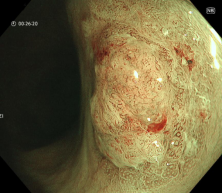

图示:食管早癌在内镜下NBI观察呈片状褐色改变,ME-NBI观察,微血管扭曲、紊乱